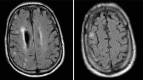

Background: Stroke is the fourth leading cause of death in the United States, leading to devastating disability. Most strokes are ischemic, and nearly one-third of these are caused by carotid disease. The primary mechanism of carotid-related stroke is an atheroembolic event from an unstable atherosclerotic plaque rupture. In the 1990s, randomized trials demonstrated the benefit of carotid endarterectomy (CEA) in reducing the risk of stroke in both symptomatic and asymptomatic carotid disease.

Results: In 2010, 2 large trials demonstrated the efficacy of CAS in select patients, although CAS was associated with an increased procedural stroke risk compared to CEA. An age effect was observed; patients >75 years do worse with CAS compared to CEA. As BMT has evolved in the past decade, a future trial (CREST-2) will address whether BMT is equal to intervention (CEA or CAS) in asymptomatic carotid disease. In a subgroup of patients with asymptomatic carotid disease, CEA plus BMT will likely remain the mainstay therapy for carotid disease compared to BMT alone. CEA and CAS will continue to play complementary roles in the future, as CAS will be done in select patients in whom CEA cannot be undertaken because of high-risk anatomical or medical conditions. Finally, a role for urgent carotid interventions in a select group of patients who present with acute neurologic symptoms is developing as a way to prevent recurrent stroke after an initial carotid plaque rupture event.